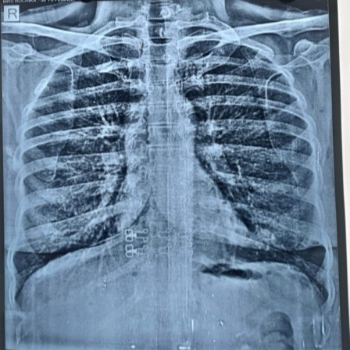

Transforming Lives with Precision The Role of X-Ray Services at Prime Hospital

1. State-of-the-Art Technology Prime Hospital boasts cutting-edge X-Ray equipment, ensuring high-quality imaging and accurate diagnoses.

Real Stories, Real Impact

Priya's story is just one example of how Prime Hospital's X-Ray services are making a difference in the lives of countless individuals. Whether it's Ramesh, a 45-year-old construction worker who needed a quick diagnosis for a potential fracture, or Meera, a 60-year-old grandmother requiring a chest X-Ray, our services have consistently delivered accurate and timely results.